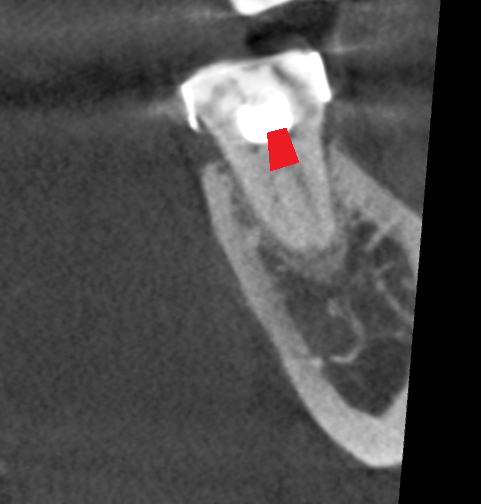

#37 mesial root coronal slice.

The coronal slice of the mesial root clearly showed the singular mesial canal dividing into two in the coronal 1/3.

Red dot - Gouge created in the floor of pulp chamber in attempt to search for the ML orifice.

Yellow Line - Single canal dividing to two in the coronal 1/3 of root (Vertucci class V classification)

With guidance from the CBCT, I enlarged the mesial orifice with gates glidden and #15 round pulp burs until the orifice was wide enough to allow me to visualise both the MB and ML canals under magnification. Following this, the case could be completed routinely. The CBCT helped me to avoid the danger area and create further iatrogenic gouging at the floor of the pulp chamber (red line below). This would have been where I would normal expect to find a ML orifice.